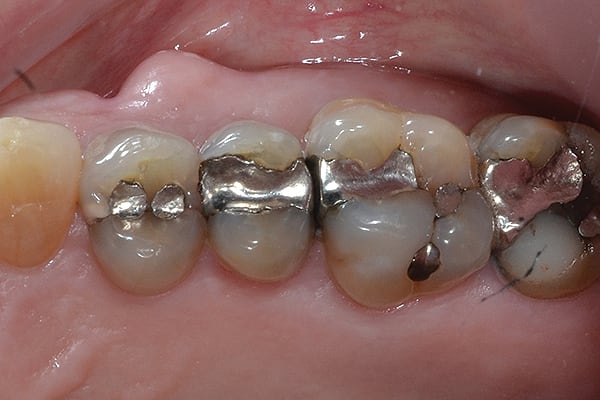

11. (Case 2) In this case, the patient presented with teeth Nos. 4-MOD and 5-MO composite resin restorations to be completed. The DENTSPLY Caulk Class II Total Practice Solution helped the author maintain efficiency by allowing both restorations to be completed together.

12. The preparations were isolated using the Palodent® Plus Sectional Matrix System. Note that multiple surfaces and teeth can be isolated at the same time, allowing practitioners to restore multiple areas without changing or repositioning the matrices.

13. The final restorations on teeth Nos. 4 and 5. Note the excellent contour and interproximal contacts achieved. In the author’s practice, completing multiple composite restorations like this can be very time-consuming when using traditional matrix systems. However, the Palodent® Plus Sectional Matrix combined with the other Class II solution products enables efficiency and uncompromised clinical outcomes.